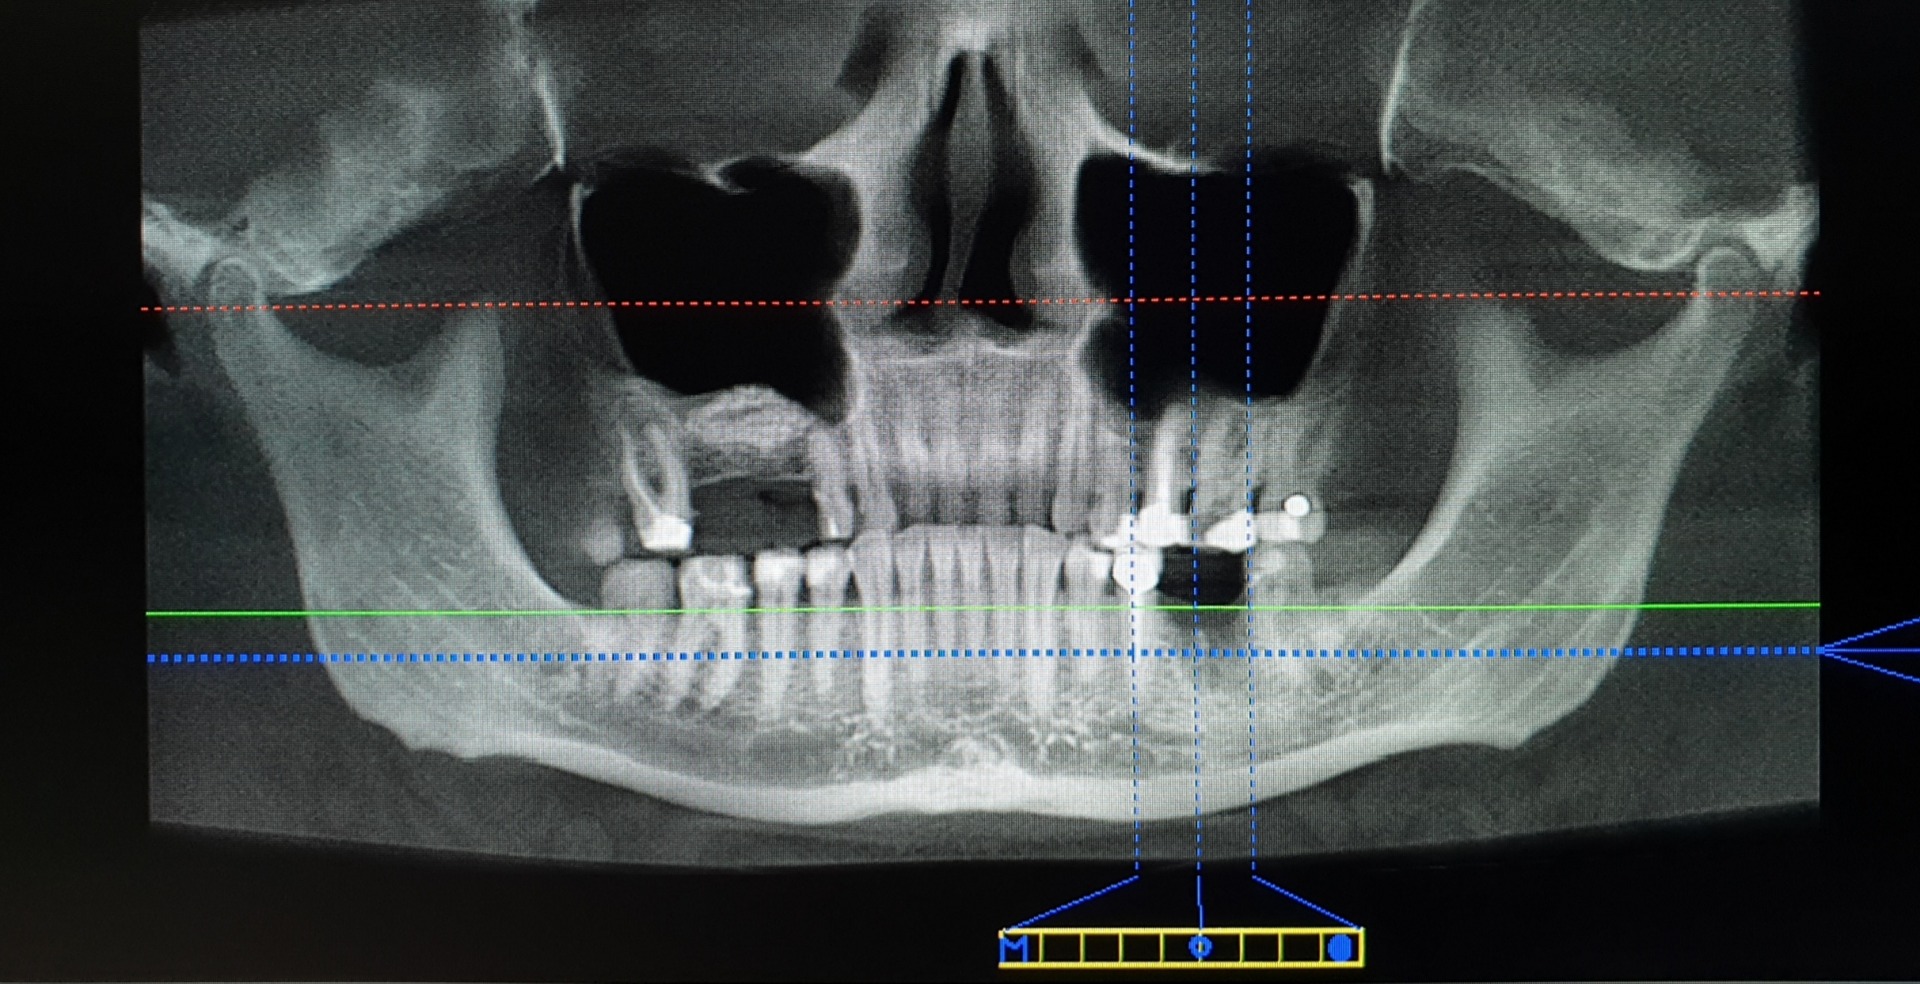

Implantat

Implantate sind künstliche, zumeist aus Titan gefertigte Zahnwurzeln die vom Zahnarzt im Knochen fest verankert werden. Sind diese Zahnimplantate erst einmal fest im Mund verwachsen, kann jeder erdenkliche Zahnersatz darauf angefertigt werden.

Im Extremfall fehlt einem Patienten nur ein Zahn, dann kann dieser mit einer Krone auf Implantat ersetzt werden.

Fehlen mehrere Zähne nebeneinander, kann auf zwei oder mehr Implantaten eine Brücke angefertigt werden.

Fehlen sehr viele oder gar alle Zähne, kann auf diesen Implantaten eine Vollprothese oder Teilprothese angefertigt werden. Da Implantate verlorene Wurzeln wieder ersetzen, gibt es im Grunde keine Einschränkung der Möglichkeiten, es sei denn die Knochensubstanz verhindert ein setzen eines Implantates. Theoretisch ist es jedoch möglich, jeden einzelnen verloren gegangenen Zahn zu ersetzen.